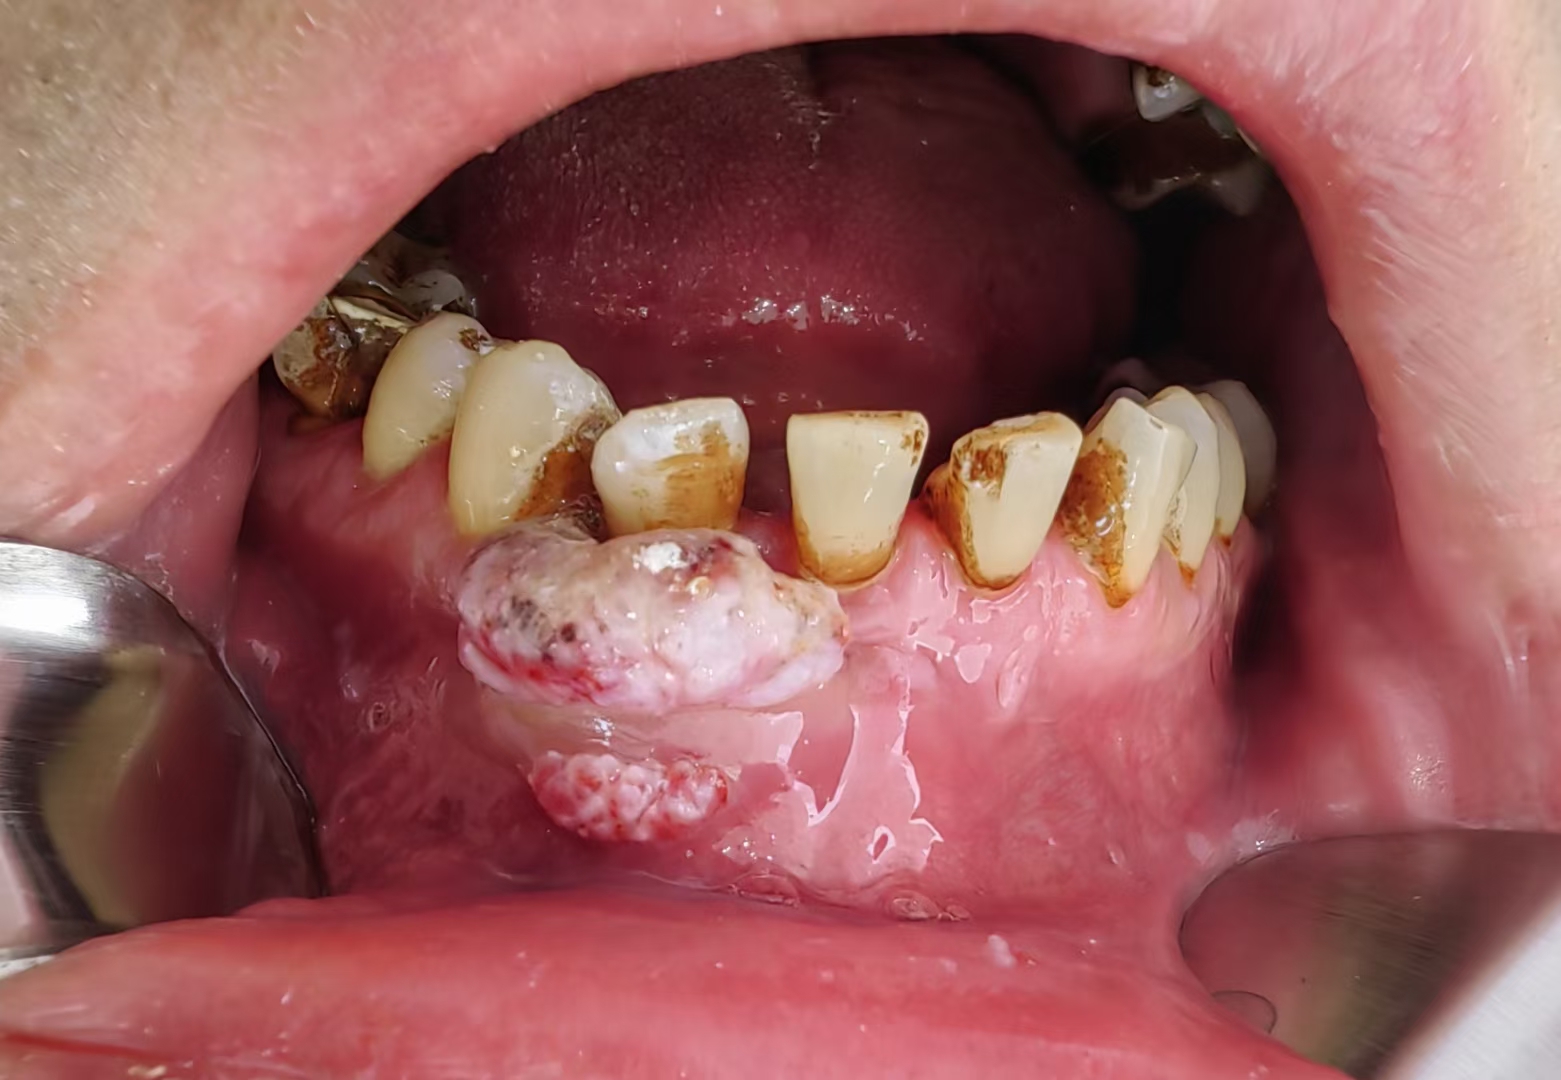

牙龈癌

牙龈癌,各种奇葩,无法描述